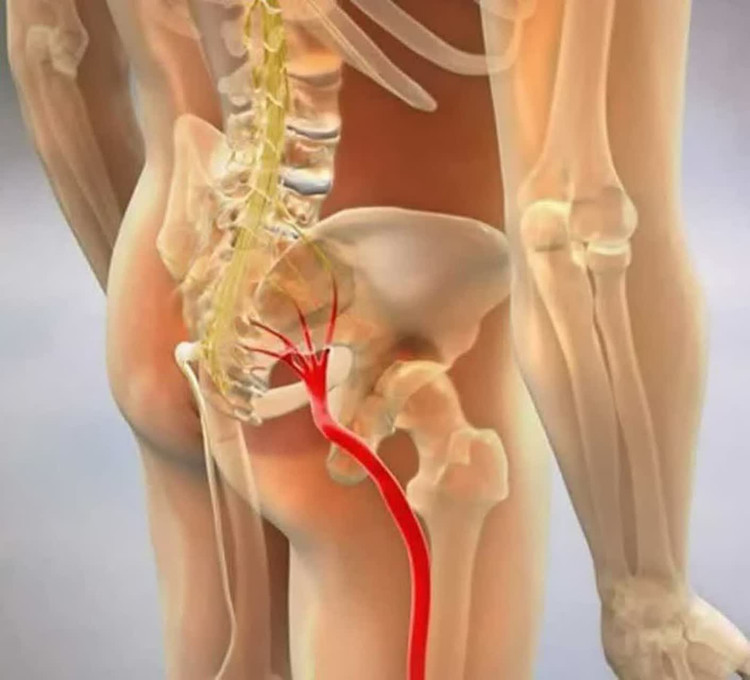

دردهای مفصلی: از جمله آرتروز و روماتیسم، زانو درد، کمردرد، سیاتیک، گردندرد و درد شانه

بازخورد مصرفکنندگان نیز عمدتاً مثبت بوده است. بسیاری از کاربران گزارش کردهاند که پس از سالها تحمل دردهای شدیدی مانند کمردرد، سیاتیک یا زانو درد، با مصرف روغن درمکسیر در مدت کوتاهی تسکین قابلتوجهی را تجربه کردهاند. حتی در مواردی مشاهده شده که تنها با یک مرتبه استفاده از روغن، درد به طور کامل از بین رفته است.. البته در برخی افراد، در روزهای ابتدایی مصرف ممکن است احساس افزایش موقت درد یا خارش در محل استعمال رخ دهد که ناشی از افزایش گردش خون موضعی بوده و به گفته متخصصان جای نگرانی ندارد.. این واکنش گذرا معمولاً پس از مدت کوتاهی برطرف میشود و در واقع نشاندهنده شروع فرآیند درمان در آن ناحیه است.

این روغن حاوی ترکیبات ضدالتهاب و ضددرد قوی (مانند عصاره زنجبیل و زردچوبه) است که با نفوذ سریع به بافت، باعث کاهش التهاب و افزایش گردش خون موضعی میشوند. بدین ترتیب درد عضله یا مفصل در آن ناحیه به سرعت فروکش میکند. فناوری نانو بهکاررفته در روغن درمکسیر نیز موجب جذب چندبرابری مواد مؤثره از طریق پوست شده و اثربخشی آن را افزایش میدهد.